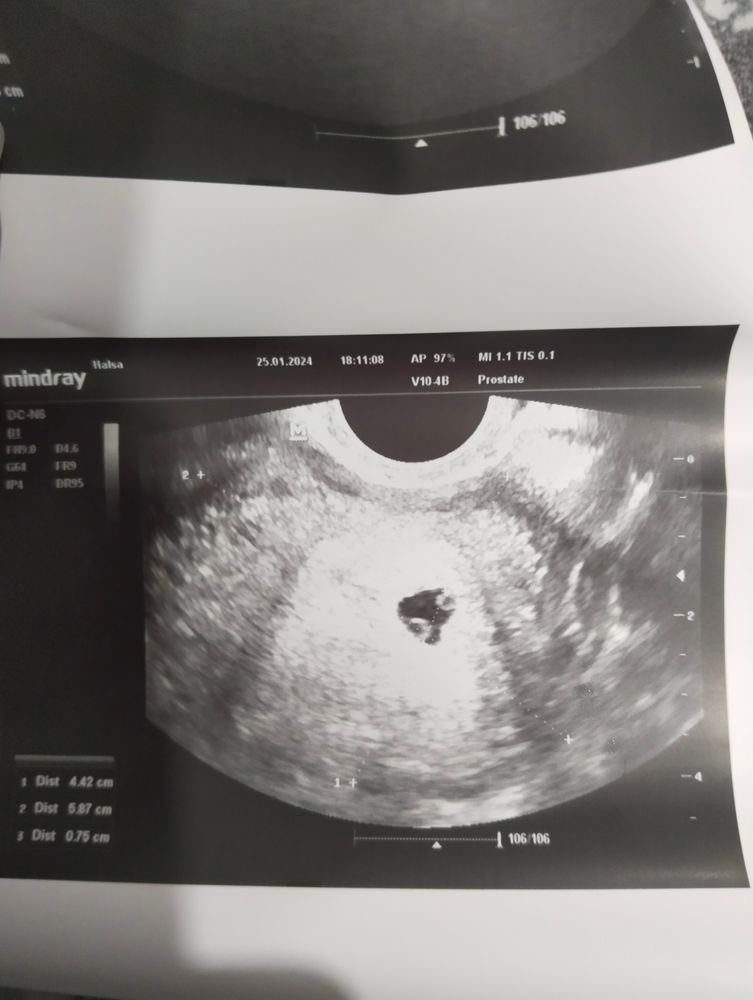

Последний месячные были 18.12. , дата зачатия 02.01 ,18.01 тест показал яркие две полоски. Сегодня (25.01) пошла на УЗИ. Беременность подтвердили. Но врач сказал ,что по УЗИ, похоже на двойню.

.Срок очень маленький 4-5 недель ,назначали УЗИ через неделю.Но очень переживаю...У мужа в роду двойни не было,а у меня была двойня у про бабушки.

Очень похоже на близнецов,через неделю уже наверняка скажут.Моих на 5 увидели.Тоже было 2 круглешка,только чётче видно.

Ну тут да, по ходу 2. Потому как ЖМ и Эмбрион, прям вместе, а тут 2 ЖМ, по идеи значит должны появится 2 эмбриона

Я бы сказала на близнецов похоже. Двойня же обычно в разных местах крепится и мешочки разные